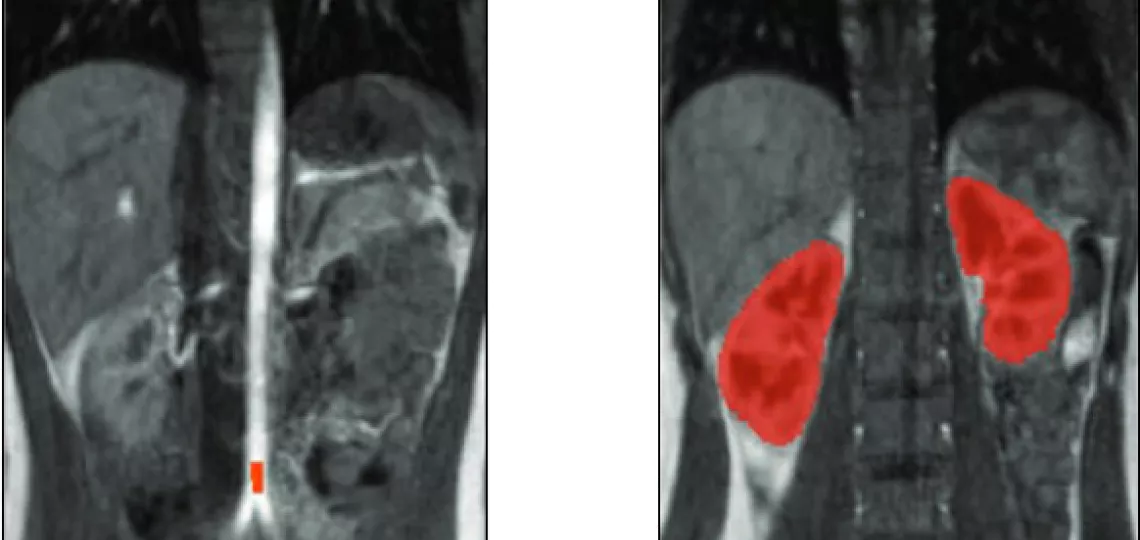

Przykładowe obrazy DCE-MRI oraz wynik wstępnej segmentacji nerek.